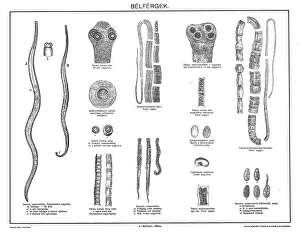

"Worms: From Martin Luther to Earth's Unsung Heroes" In the annals of history, one cannot overlook the significance of worms. These seemingly insignificant creatures have left their mark in various realms, from religion to ecology. Let us embark on a journey through time and nature as we explore the diverse world of worms. Centuries ago, in 1521, German religious reformer Martin Luther defended himself before Holy Roman Emperor Charles V at the Diet in Worms. This historic event shaped the course of Christianity and paved the way for religious freedom. While Luther fought his battles with words, gastrointestinal nematodes waged their own silent war within our bodies. These tiny they are cause havoc in our digestive systems if not properly addressed. Delving deeper underground, we discover mole-eating worms diligently burrowing through soil. Their tireless efforts contribute to aerating and enriching the earth beneath our feet, ensuring healthy ecosystems thrive. Meanwhile, song thrushes proudly display their hunting prowess by clutching wriggling worms in their beaks. These melodious birds rely on these nutritious morsels to sustain themselves and nurture their young. Turning towards sustainable practices, compost wormeries offer a glimpse into nature's recycling system. Within black plastic bins filled with kitchen waste lies a bustling community of earthworms diligently breaking down vegetable peelings and cardboard into nutrient-rich compost. Venturing further below ground level reveals intricate tunnels created by earthworms that enhance soil structure while providing essential aeration for plant roots. The symbiotic relationship between these humble creatures and grass roots ensures flourishing green landscapes. Yet even coral polyps residing amidst vibrant reefs are not immune to wormy encounters; they feast upon polychaete worms under cover of nightfall—nature's carnivorous ballet unfolding beneath tranquil waters off Australia's Great Barrier Reef. On land once again but far from serene waters lies Colorado where barred tiger salamanders indulge in an earthworm feast.